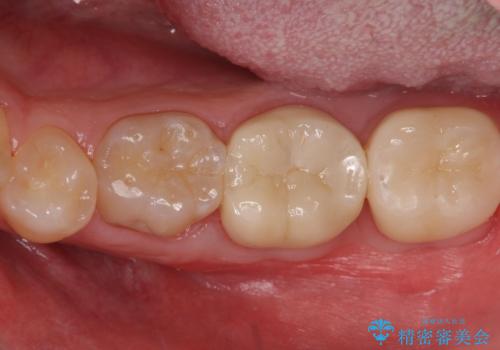

- 口の中を予算の範囲内でできるだけきれいにしたいとのことで来院された患者様です。

矯正治療と虫歯治療を組み合わせてご提案しましたが、ご予算との兼ね合いで虫歯治療のみを行うこととなりました。

奥歯は十分な歯の高さがなかったため、クラウンをかぶせる前に歯周外科治療で歯の高さを出しています。

歯科に通うようになってから磨き残しの状態も改善されていきました。